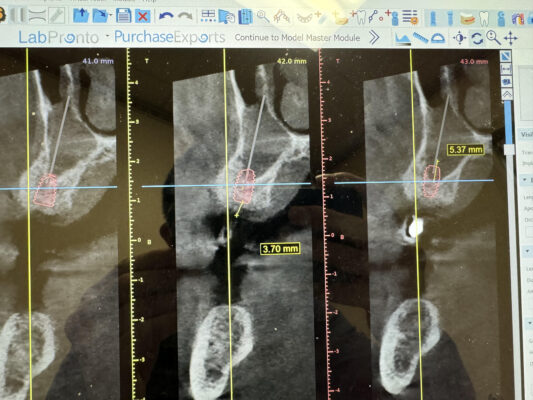

Hey everyone. I am tx planning #14 implant (5×8.5mm) with a transcrestal sinus lift of 4-5mm. He reports year round sinus issue; uses a nasal spray. I am concerned with the amount of radioopacity in the left sinus to move forward with sinus bump. His right sinus is completely clear. I put him on sudafed for 2 weeks (to try something different from his spray); took another scan but there is no improvement in the volume of radioopacity. I suggested that he visit his ENT for further consult in preparation for the implant and bump. What are your thoughts?

It very well could be a mucus retained cyst (very common) which typically we don’t do anything for unless you need to do a sinus lift, and that can be physically removed doing a lateral window and if you don’t want to take that on you could have the ENT remove that so it is clear and will give you a better opportunity to do a proper Crestal sinus lift.